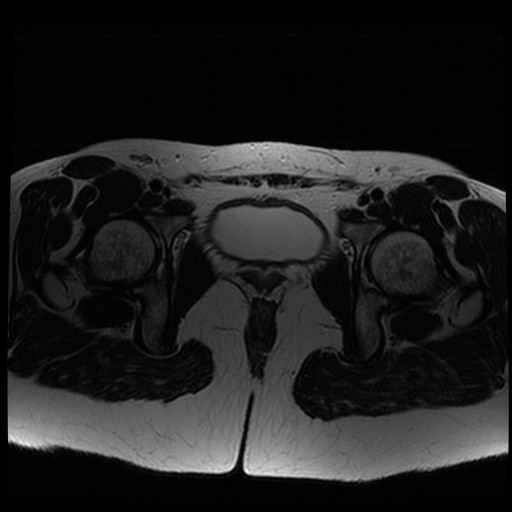

Bekken